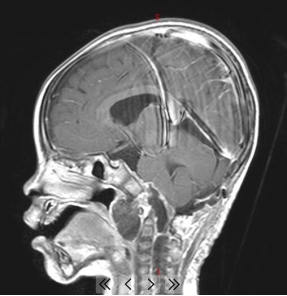

通常情况下,小孩子很少打鼾(俗称打呼噜),如果您的宝宝睡觉打鼾,并且声音很大,那要引起注意了,最好带孩子做个检查,因为睡觉打鼾也有可能是脑肿瘤引起的。